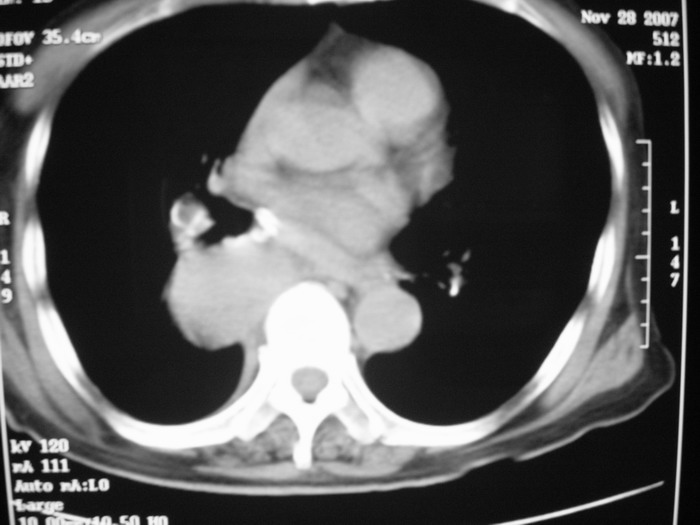

m、70y,反复咳嗽2月。请各位同仁给定位1、(肺?,纵隔?)2、定性。感谢!!

右后纵隔良性占位性病变,神经原性肿瘤可能性大,就其形态看,高密度囊肿待排,建议mri检查。

正位看,支气管分叉角度增大,来源考虑后纵隔的占位,性质考虑1.神经源性肿瘤2.肿大淋巴结

右下肺纵隔旁较大 均匀密度肿块,部分边缘植入纵隔,气管明显受压 变形。支持:后纵隔肿瘤!首选:神经源性!不支持肺内肿瘤原因:1 肿瘤位于下叶支气管及背段支气管开口区,但未侵犯支气管,只是受压表现。2 纵隔内未见肿大淋巴结。3 肺内未见阻塞性肺炎。

支持后纵隔肿瘤,病灶大体呈“滴状”与支气管关系密切,考虑:1.高密度支气管囊肿,2.神经纤维瘤。增强有鉴别意义。